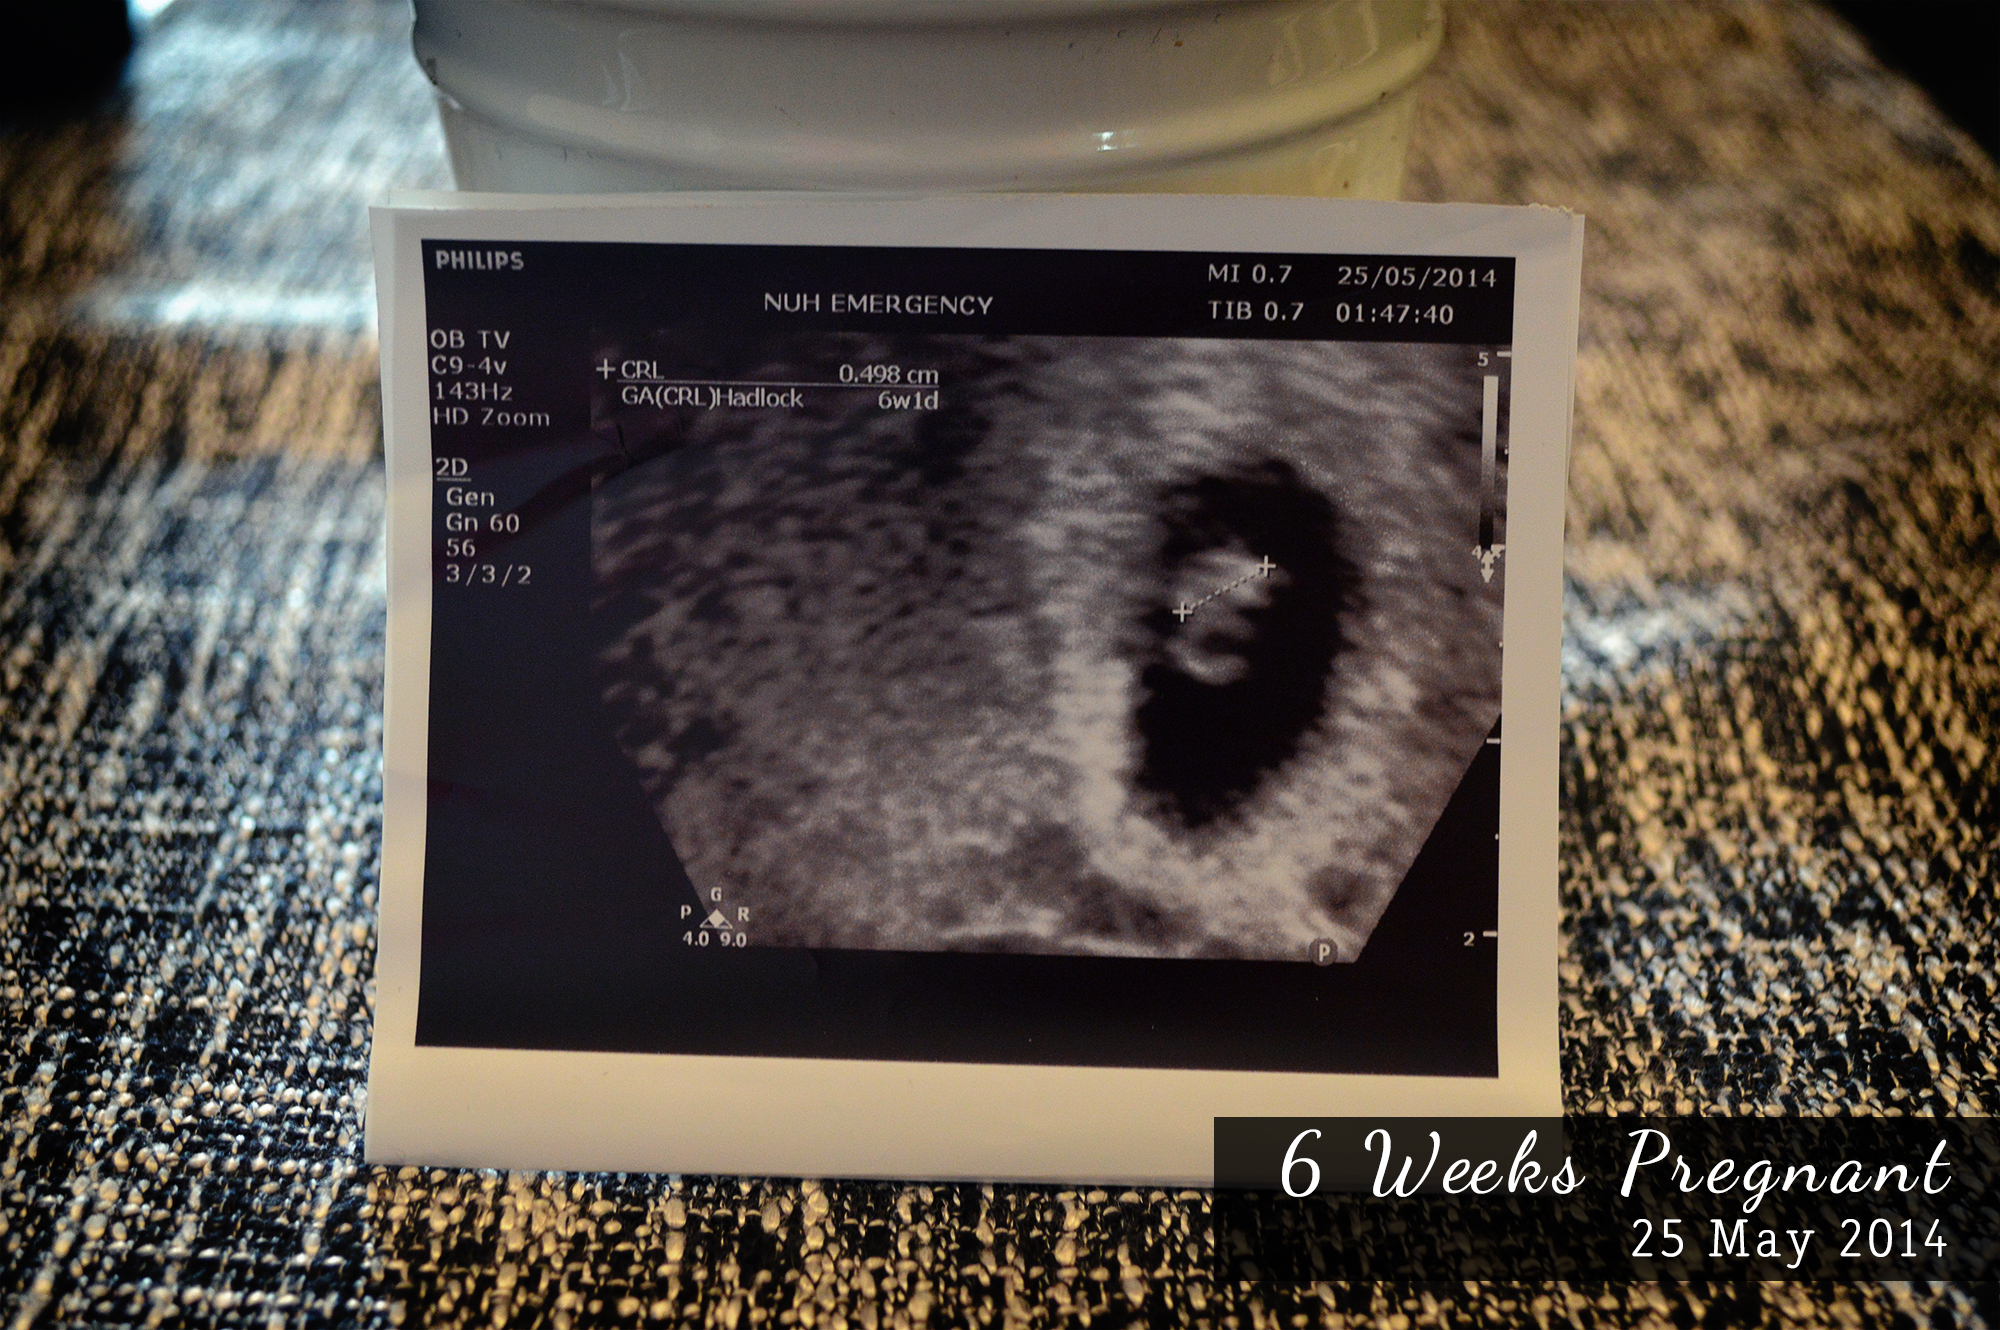

I was compiling all my Ultrasound scan pictures earlier and was amazed at how fast baby is growing.

6 Weeks the tiny little being we 1st saw.